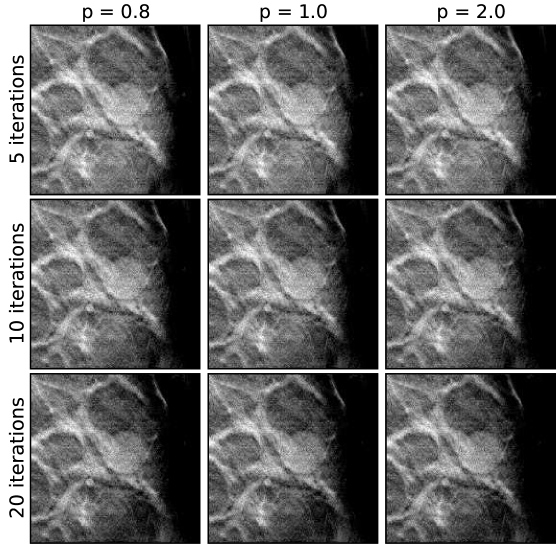

Each of the three cases, below, are reconstructed in the same way, meaning the same sets of algorithm parameters are used. The exceptions to this are that the image volume dimensions and the projection data cropping are slightly different for each case. For the EM results images are shown at 5,10, and 20 iterations, as iteration number is really the main control for regularization. For ASD-POCS, the objection function parameter is set to 0.8, 1.0, and 2.0; lower values of tend to sharpen edges. The relaxation factor takes on values of 1.0, 0.5, and 0.1; smaller , in general, allows for ASD-POCS to achieve lower values of the TpV objective. Images for ASD-POCS are also shown for 5, 10, and 20 iterations. As will be seen, there is surprisingly little change in the reconstructed images for these iteration numbers. In each of the image sets, a 2D ROI is displayed that shows either microcalcifications or a mass, depending on the case.

V.4 Case 1: microcalcifications

A set of EM images for the first case is shown in Fig. 4, and the corresponding ASD-POCS images are shown in Figs. 5, 6, and 7. A striking feature of the ASD-POCS reconstructions is the prominence of the microcalcifications. Lower values of accentuate these small features better than large -values. Even for , the visibility of the microcalcifications is comparable to that of the EM results. The differences in microcalcification contrast can be seen quantitatively in the profiles shown in Fig. 8. These profiles are plotted along depth and transverse lines that intersect with a single microcalcification. We point out that while lower increases regularization strength in ASD-POCS and lower iteration number increases regularization strength for EM, there is no direct correspondence between the two parameters; the chosen iteration numbers for the EM profiles are selected only for reference. Interestingly, there seems to be little change in the ASD-POCS image for iteration numbers 5-20, which obviously has some practical implication.

From the profiles and slice images, it is clear that lower in ASD-POCS enhances microcalcification contrast substantially, leaving one to wonder if there is any advantage to larger -values. While lower -values appear to be advantageous, there is also an impact of -value on the image background. The ROIs displayed in Figs. 5, 6, and 7 are shown in a large enough region to obtain some sense of the difference in background. Again, we are trying, here, to only give some intuition on the parameter-space dependence of the ASD-POCS algorithm. Optimal values of and for particular tasks, such as microcalcification detection by human observers, need to be investigated in separate studies. Another important factor that affects selection of and is data quality. Lower values of , for example, may be robust against detector noise, but may be also more sensitive to inconsistency due to patient motion.